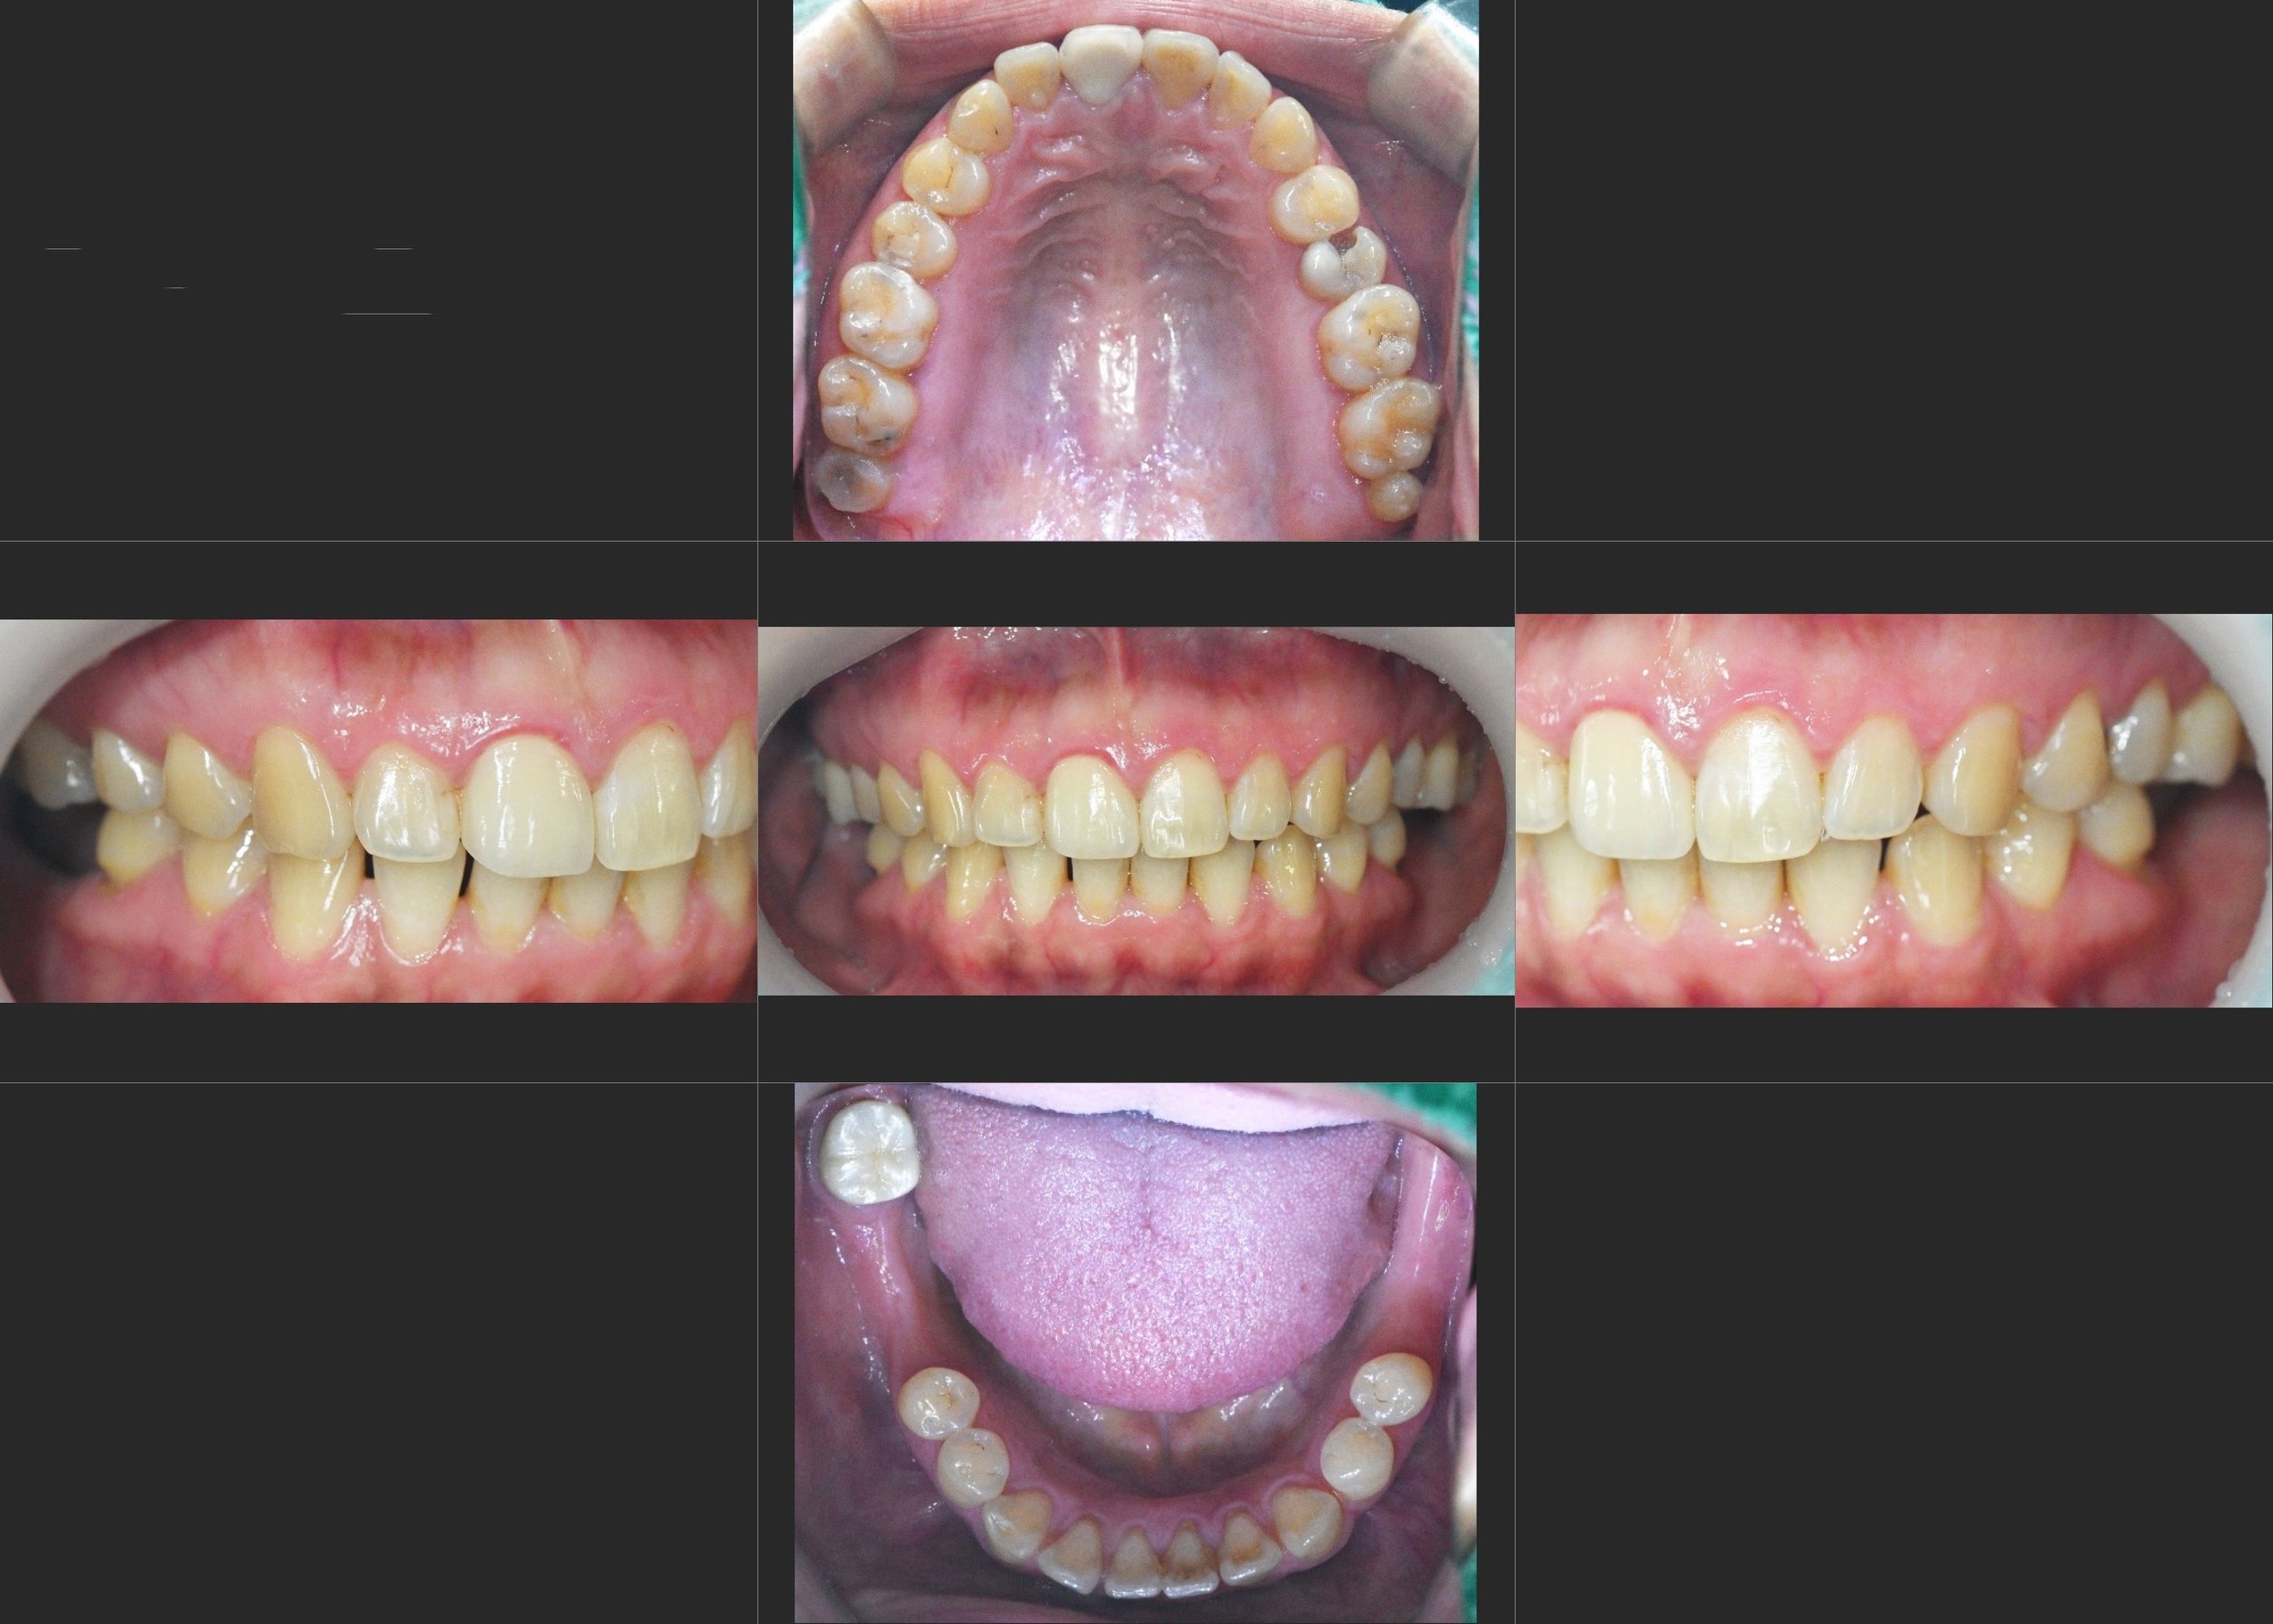

A female patient in her 30s presented with chronic TMJ discomfort and a noticeable shifting of the jaw upon closure. Clinical and radiographic evaluation revealed a complex occlusal disharmony:

• Posterior Bite Collapse & Supra-eruption: The long-term loss of mandibular posterior teeth had allowed the opposing maxillary molars to erupt downward (supra-eruption), disrupting the occlusal plane.

• Pathological Mandibular Deviation: A premature contact at tooth #48 acted as a functional interference, forcing the mandible to deviate from its natural path during closure.

• TMJ Dysfunction: This constant displacement had led to chronic muscle tension and symptomatic TMJ distress, significantly impacting the patient's quality of life.

INTRA ORAL - BEFORE